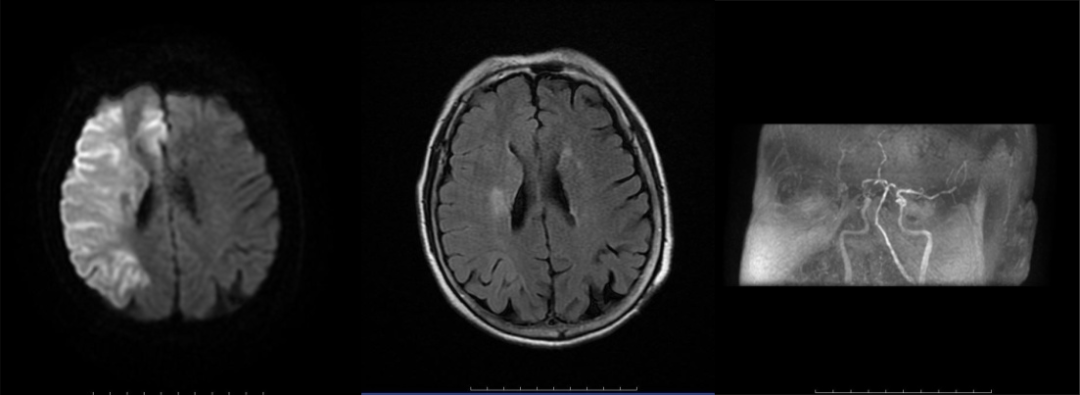

病历一:患者,71岁女性,因突发左侧肢体无力9小时,并伴有进行性意识障碍入院,经急诊MRI检查初步诊断为脑梗死。

神经内科介入团队接诊患者后迅速作出响应,实施造影,并采用Solitaire取栓支架及抽吸导管负压抽吸,成功取出条块状暗红色血栓。

右侧大脑中动脉起始部闭塞,右侧大脑中动脉开通,取出血栓。